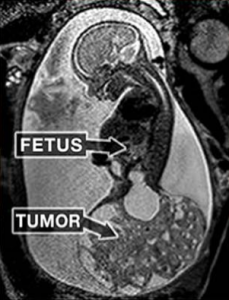

Macie has a unique story. At 23 weeks in utero, doctors discovered a grapefruit-size tumor growing on her. Without intervention, she was predicted to die.

At 25 weeks, surgeons from Texas Children’s Fetal Center operated on Macie, leaving just her head and upper body inside her mother’s womb as they operated, removing the growth.

Macie stayed safe inside for another amazing ten weeks, finally being “born again” at 35 weeks. Today, she has a scar, but that’s about it; she is reported to be “perfectly healthy.”